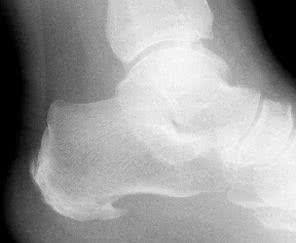

Cezary Michalak: Nazwa jest nieco myląca. Dolegliwości określane jako tzw. ostroga piętowa to tak naprawdę zapalenie przyczepu powięzi podeszwowej do kości piętowej. Nieleczony stan zapalny prowadzi do powstania złogów wapiennych, a w konsekwencji wyrośli na kości piętowej, którą nazywa się ostrogą piętową i stwierdza się w badaniu RTG. Paradoksalnie, spotyka się liczne wypadki, gdy na wykonywanych z innych przyczyn zdjęciach rentgenowskich stwierdza się obecność masywnej ostrogi piętowej - a jednocześnie pacjent nie ma żadnych dolegliwości w tej okolicy.

Cezary Michalak: Ból, przede wszystkim podczas chodzenia. Jednak dyskomfort, który odczuwa chory, jest spowodowany nie przez wyrostek kostny, widoczny na zdjęciu RTG tylko u 50% pacjentów, ale przez stan zapalny rozcięgna podeszwowego. I to właśnie on wymaga leczenia.

Cezary Michalak: Jeżeli pacjent podejrzewa, że cierpi z powodu ostrogi, powinien wybrać się do ortopedy. Na podstawie wywiadu i badania palpacyjnego stopy, czyli badania dotykiem, można zlokalizować faktyczne źródło bólu. W przypadku ostrogi piętowej będzie się ono znajdowało w okolicy środka pięty. W chorobie Haglunda, czasem mylonej z ostrogą piętową, bolesność odczuwana jest ponad piętą, w miejscu przyczepu ścięgna Achillesa. Diagnozę potwierdza zdjęcie RTG lub badanie ultrasonograficzne.